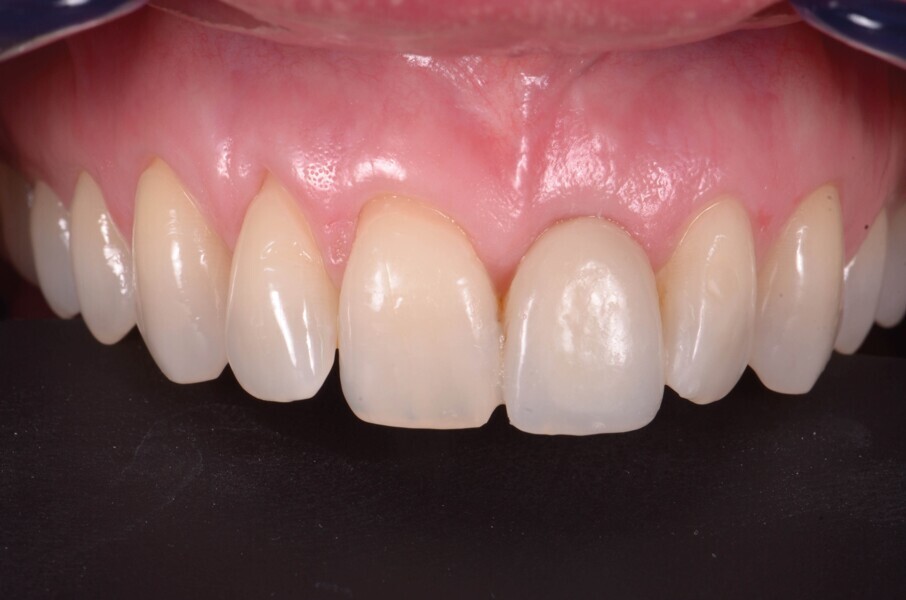

Fig. 20a : Couronne définitive implanto-portée, vue extraorale ;

Fig. 20b : Couronne définitive implanto-portée, vue occlusale.

Le transfert est donc mis en place en bouche (Fig. 18), et une empreinte est prise en technique pick-up, avec un porte-empreinte à ciel ouvert (Fig. 19). La couronne provisoire est remise en place rapidement, afin de prévenir toute rétraction des tissus mous. La couronne définitive en disilicate de lithium est ensuite mise en place (Fig. 20), et est vissée avec couple de serrage de 20 Ncm, conformément aux recommandations du fabricant.

Lors du suivi a cinq ans, on ne peut que constater le résultat esthétique maintenu (Fig. 21). La radiographie montre un niveau osseux stable et une connexion étroite entre l’implant et le pilier (Fig. 22).